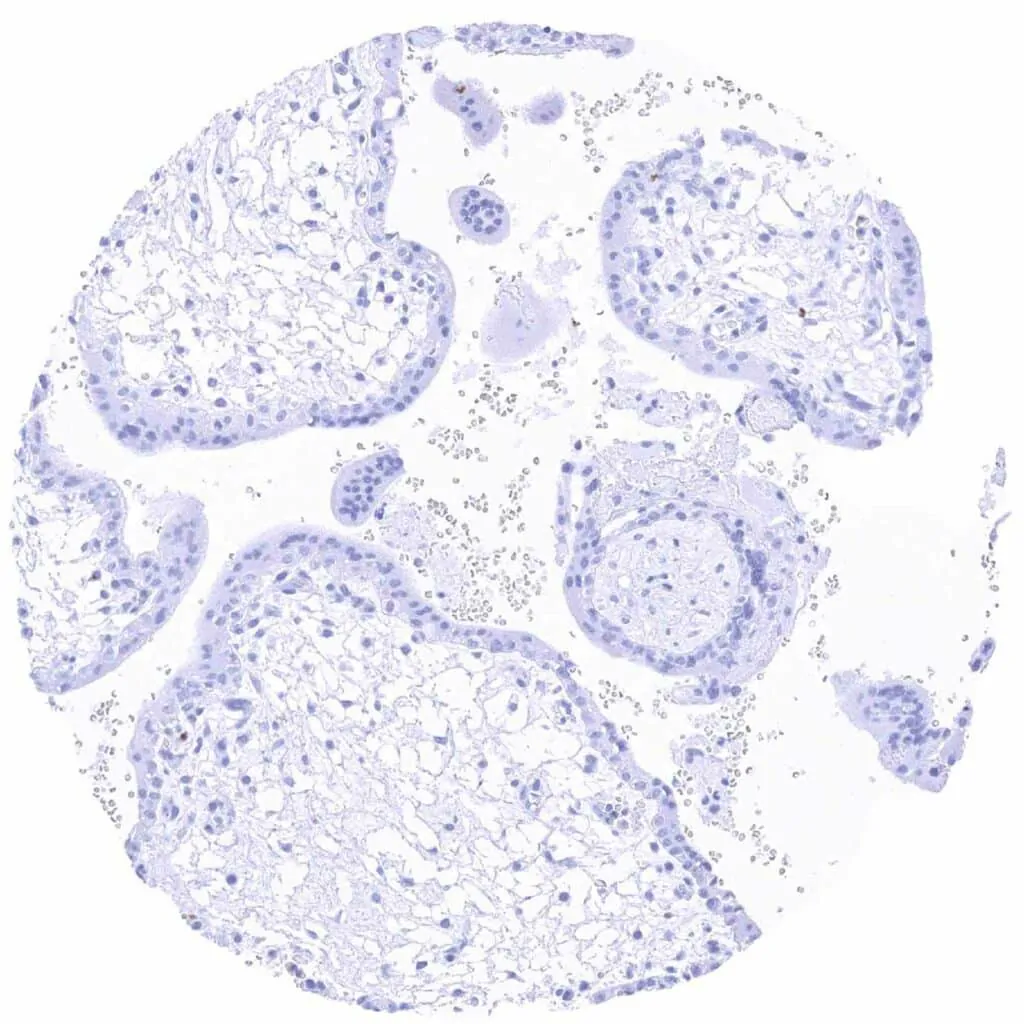

Placenta early, decidua (pregnancy)

Placenta early

Placenta, mature, amnion and chorion

Placenta, mature